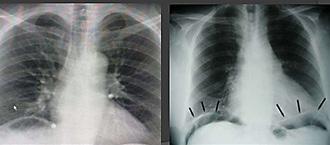

La segunda complicación más común de la úlcera péptica

Las úlceras gástricas prepilóricas → son la causa más común de perforación.

Las úlceras duodenales de la pared anterior tienen más probabilidades de perforarse que las úlceras de la pared posterior Clínica → dolor súbito, severo y rigidez abdominal (rebote +) repentinos y difusos (ENAM 2015), signo Jobert + (desaparición de matidez hepática)(ENAM 2015)

Confirma → radiografía simple toraco abdominal en bipedestación (ENAM 2011)

www.qxmedic.com GASTROENTEROLOGÍA PAG. 46

Figura 90. Signo de Jobert → desaparición de la matidez hepática → neumoperitoneo

Signos de Neumoperitoneo:

♦ Signo de Popper

♦ Singo de alas de gaviota

♦ Observación del ligamento falciforme (El aire libre puede delinear el ligamento falciforme)

Figura 91. Signos radiológicos de neumoperitoneo Figura 92.